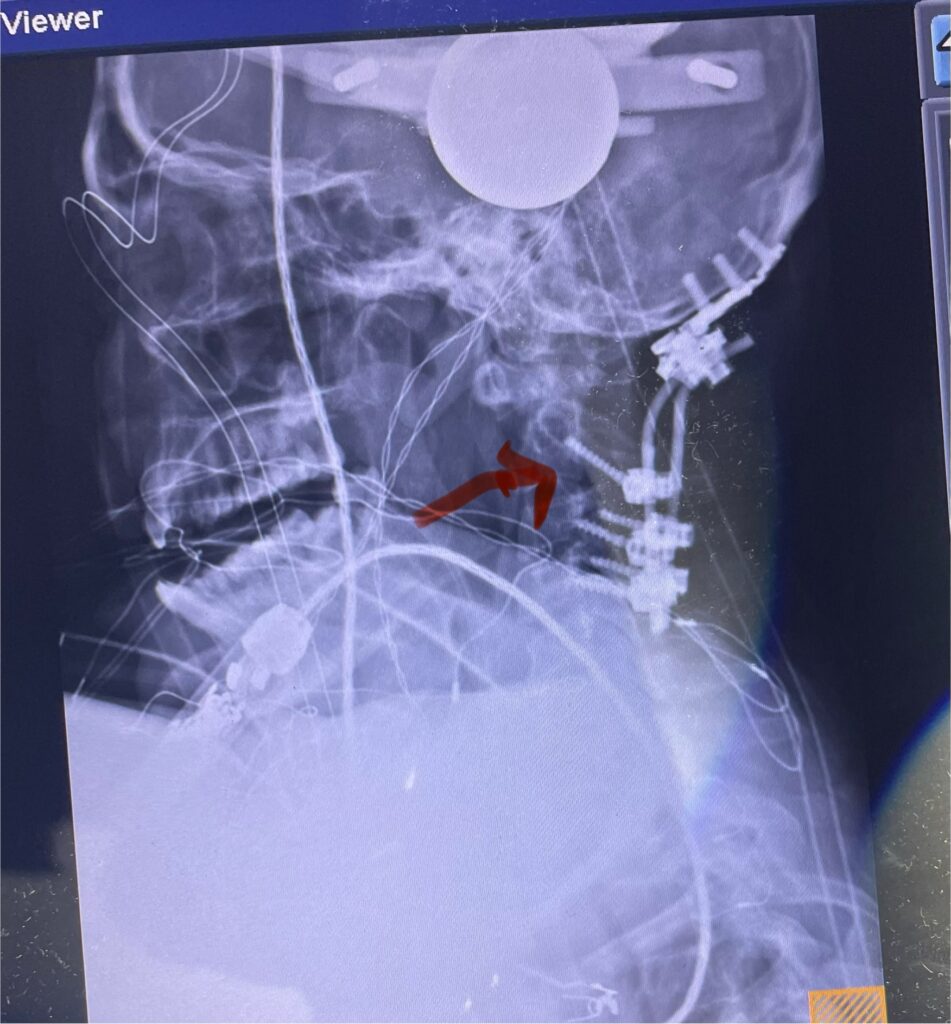

Patients may require an occipital-cervical fusion for both cranio-cervical and atlanto-axial instability, depending on the anatomy. Patients who have long segment posterior cervical fusions can sometimes […]

Here is a tough case: This is a 72 year-old male who presented with several months of progressive neck pain without symptoms of the arms or legs. […]